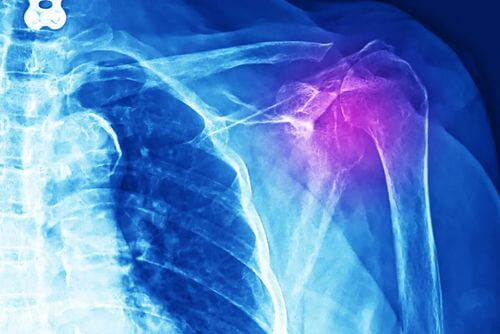

D’altra parte, per diagnosticare questa lesione, vengono eseguiti diversi esami diagnostici. Tra i più comuni ricordiamo radiografia, ecografia e risonanza magnetica.

Un altro possibile esame diagnostico è la tomografia assiale computerizzata (TAC). Inoltre, si esegue una visita medica e uno studio dettagliato dell’anamnesi del paziente.